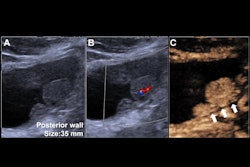

The echogenic nature of microbubbles in these agents improves ultrasound images via a strong signal-to-noise ratio and high temporal resolution that helps with imaging for blood vessels and soft tissue. CEUS proponents say the technique has advantages over other contrast imaging methods, including CT and MR exams that use gadolinium and iodine. As well, recent studies suggest that CEUS is effective in procedures such as ablation and biopsy.